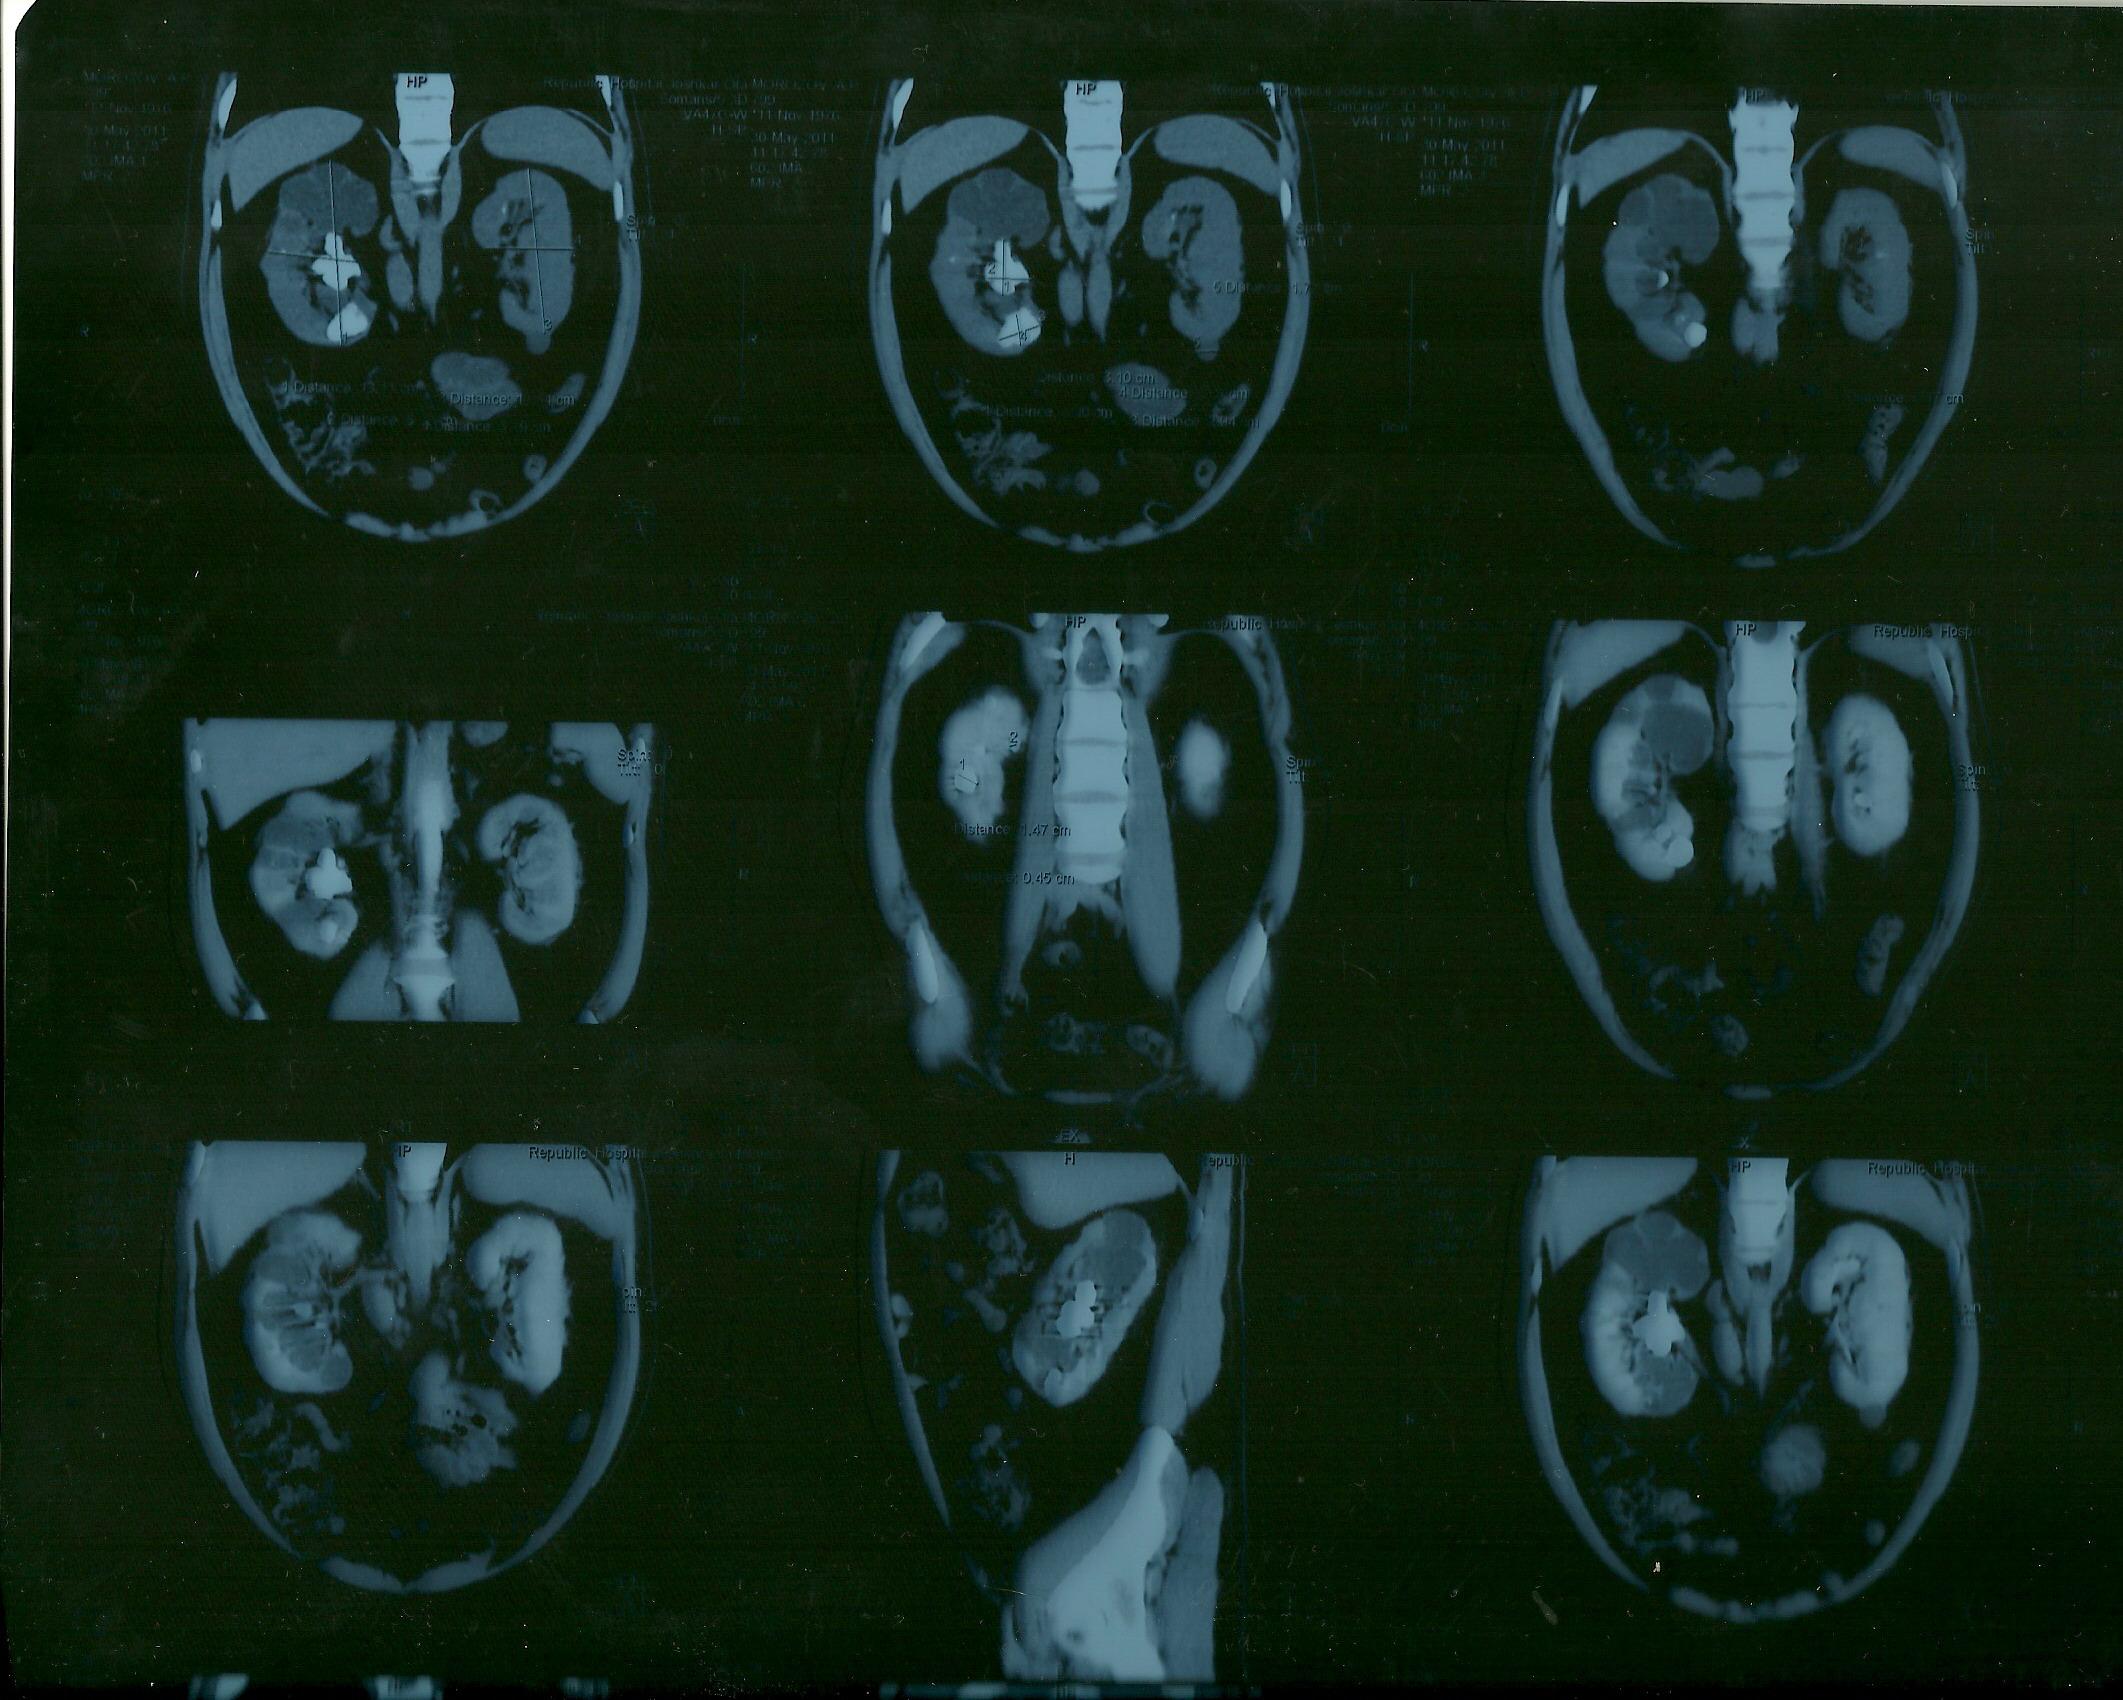

коралловидный камень

Морозов Алексей. Здравствуйте,находился

на лечении в урологическом отделении

г.Йошкар-Ола по поводу МКБ, В правой почке

обнаружен коралловидный камень,врач

рекомендовал ЧПНЛ в Нижнем Новгороде,но